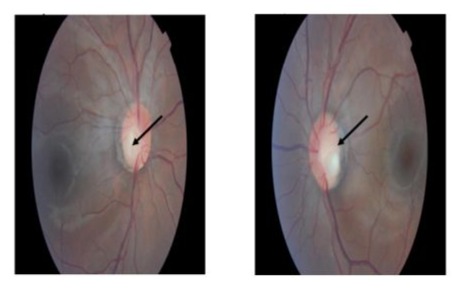

Regarding the eye examination, the fundus showed bilateral inferotemporal excavation of the optic disc or optic disc pits, with a sharp papilla, a normal macula, and unremarkable blood vessels and periphery as depicted in Figures 1&2.

Figures 1&2: Eye fundus showing optic disc pit inferotemporal of the both eyes.

Around 77% of patients with PAX2 mutations present optic nerve involvement. Affected individuals may have unilateral or bilateral optic disc anomalies ranging from an optic disc pit to a chorio-retinal coloboma. The most common alteration is optic nerve dysplasia, characterized by an enlarged optic disc with emerging peripheral vessels and cilioretinal vessels. Other described characteristics include a vacant optic nerve with a central excavation, absence of the central retinal artery, presence of multiple cilioretinal arteries in radial formation, retinal coloboma, and retro bulbar optic nerve cysts [11]. In our case report, the patient has bilateral optic disc pits, as shown in pictures 3 and 4. According to the study by Bower et al, this anomaly was found in less than 10% of patients. Other ophthalmoscopic findings include optic nerve coloboma, optic disc dysplasia, morning glory anomaly, and hypoplastic optic discs, occurring in approximately 50%, over 10%, 5%, and less than 5% of patients, respectively [11]. The Consequences of the ocular malformations include decreased visual acuity, blindness, and retinal detachment.